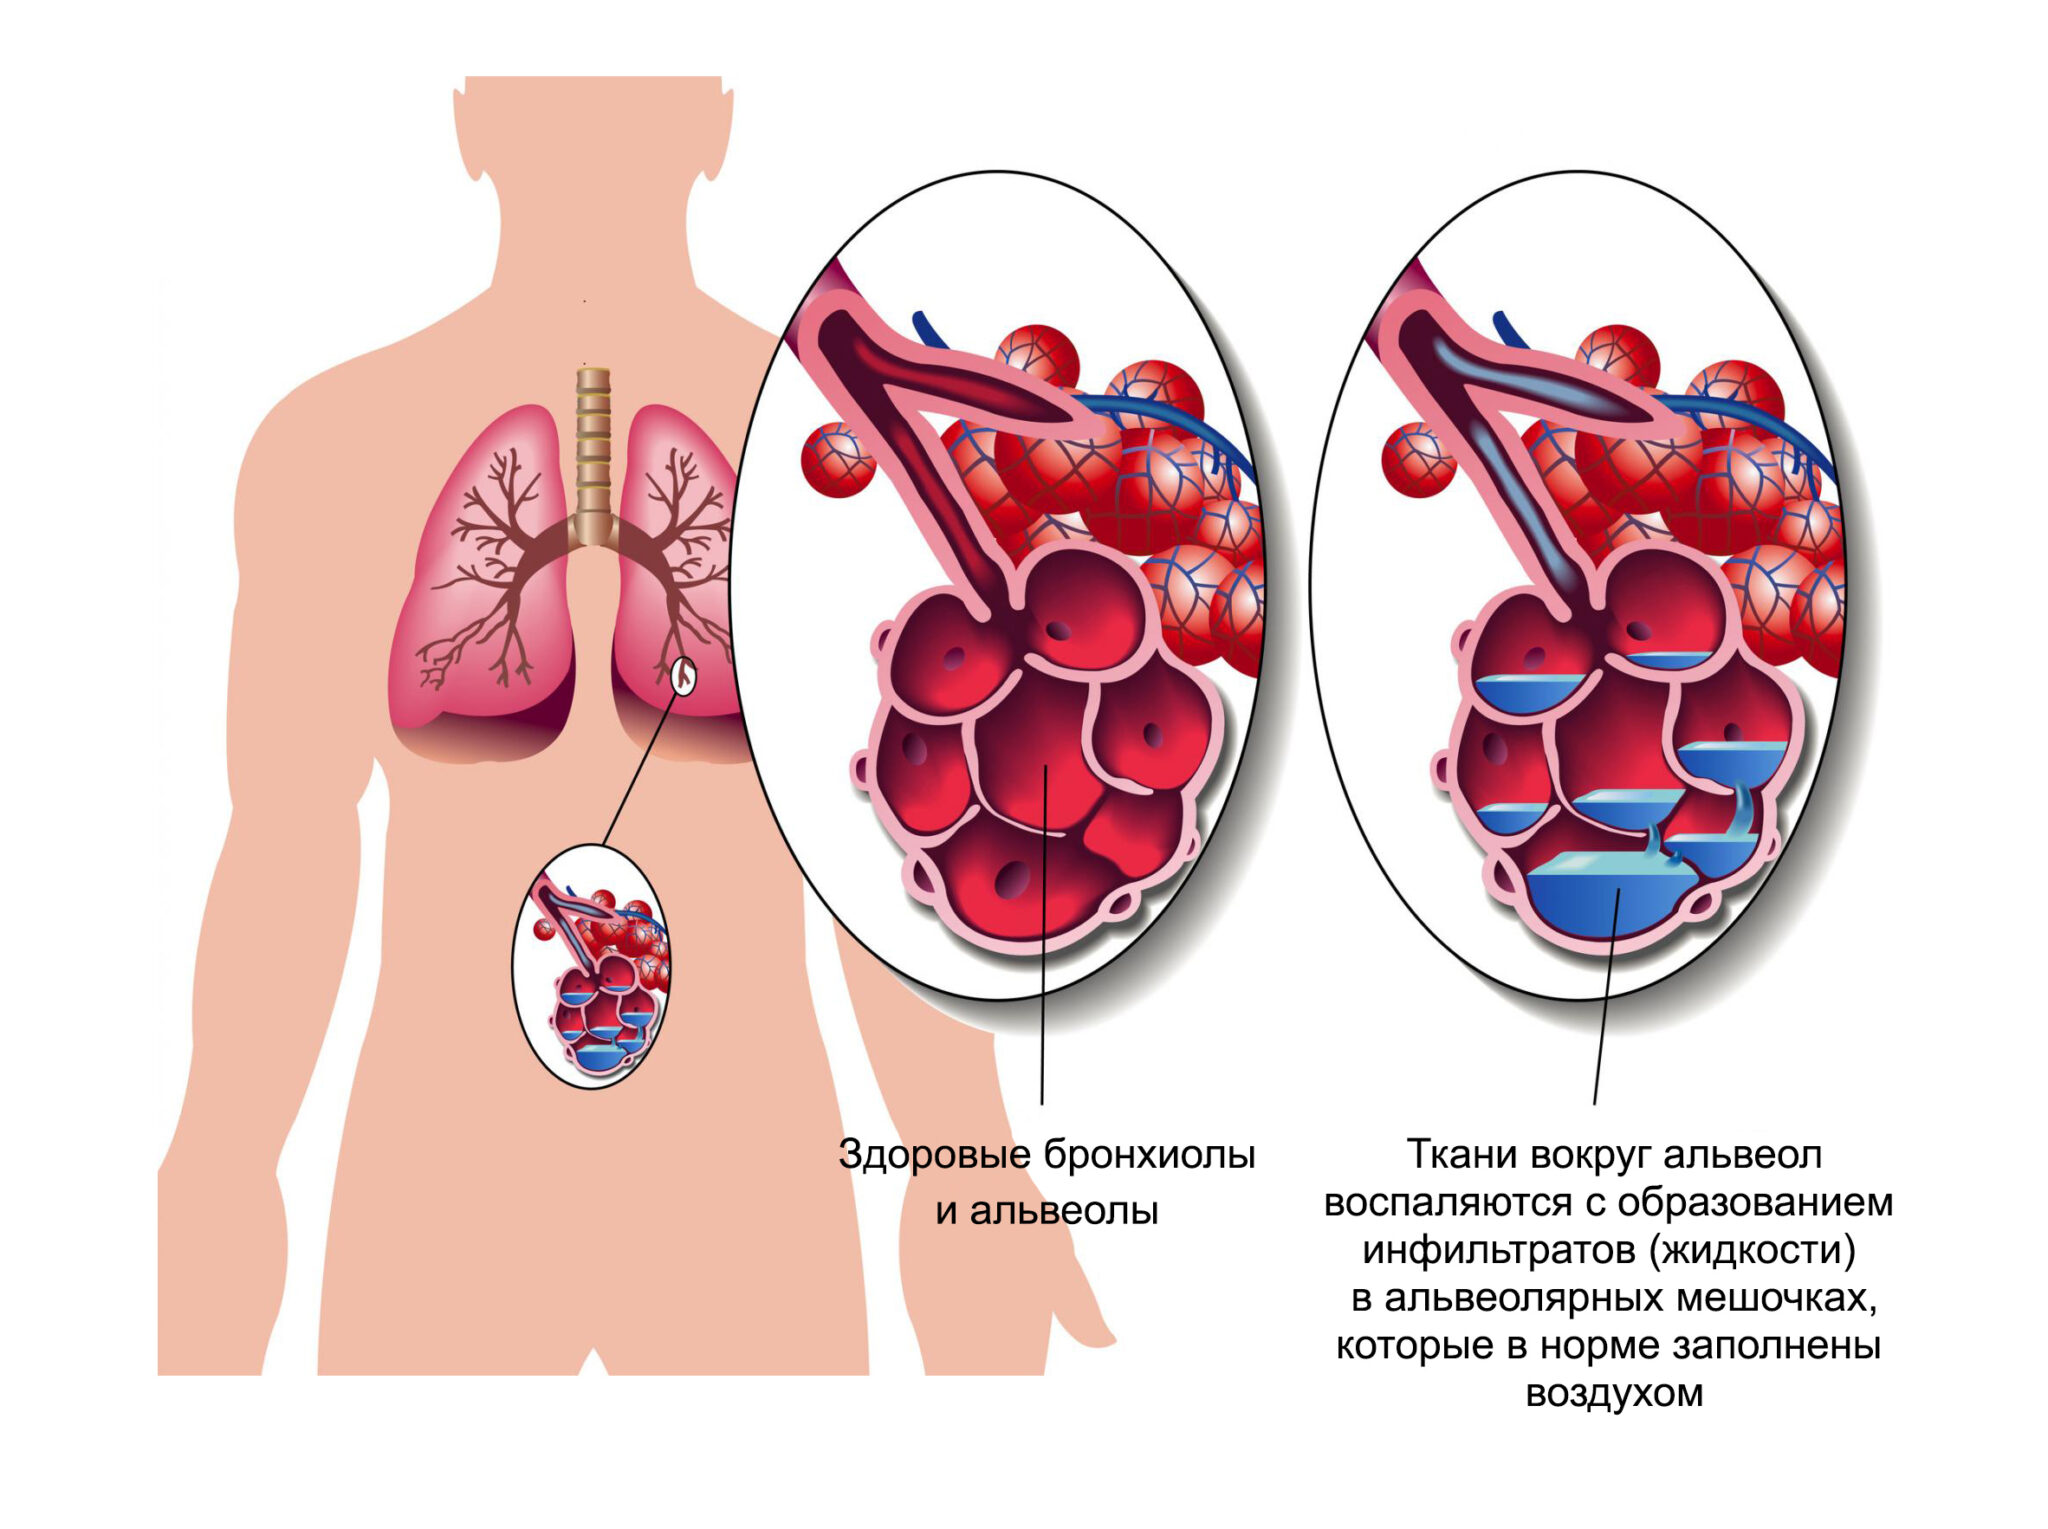

Пневмония - это серьезное заболевание легких, которое может быть вызвано различными причинами, включая бактериальные, вирусные и грибковые инфекции. Для того чтобы наглядно показать симптомы, диагностику и лечение этого заболевания, картинки могут быть очень полезны.

Картинки с симптомами пневмонии

В этом разделе представлены изображения, демонстрирующие различные симптомы пневмонии, такие как кашель, одышка, боль в груди и повышенная температура. Эти картинки могут быть использованы для обучения и презентаций в области медицины и здравоохранения.